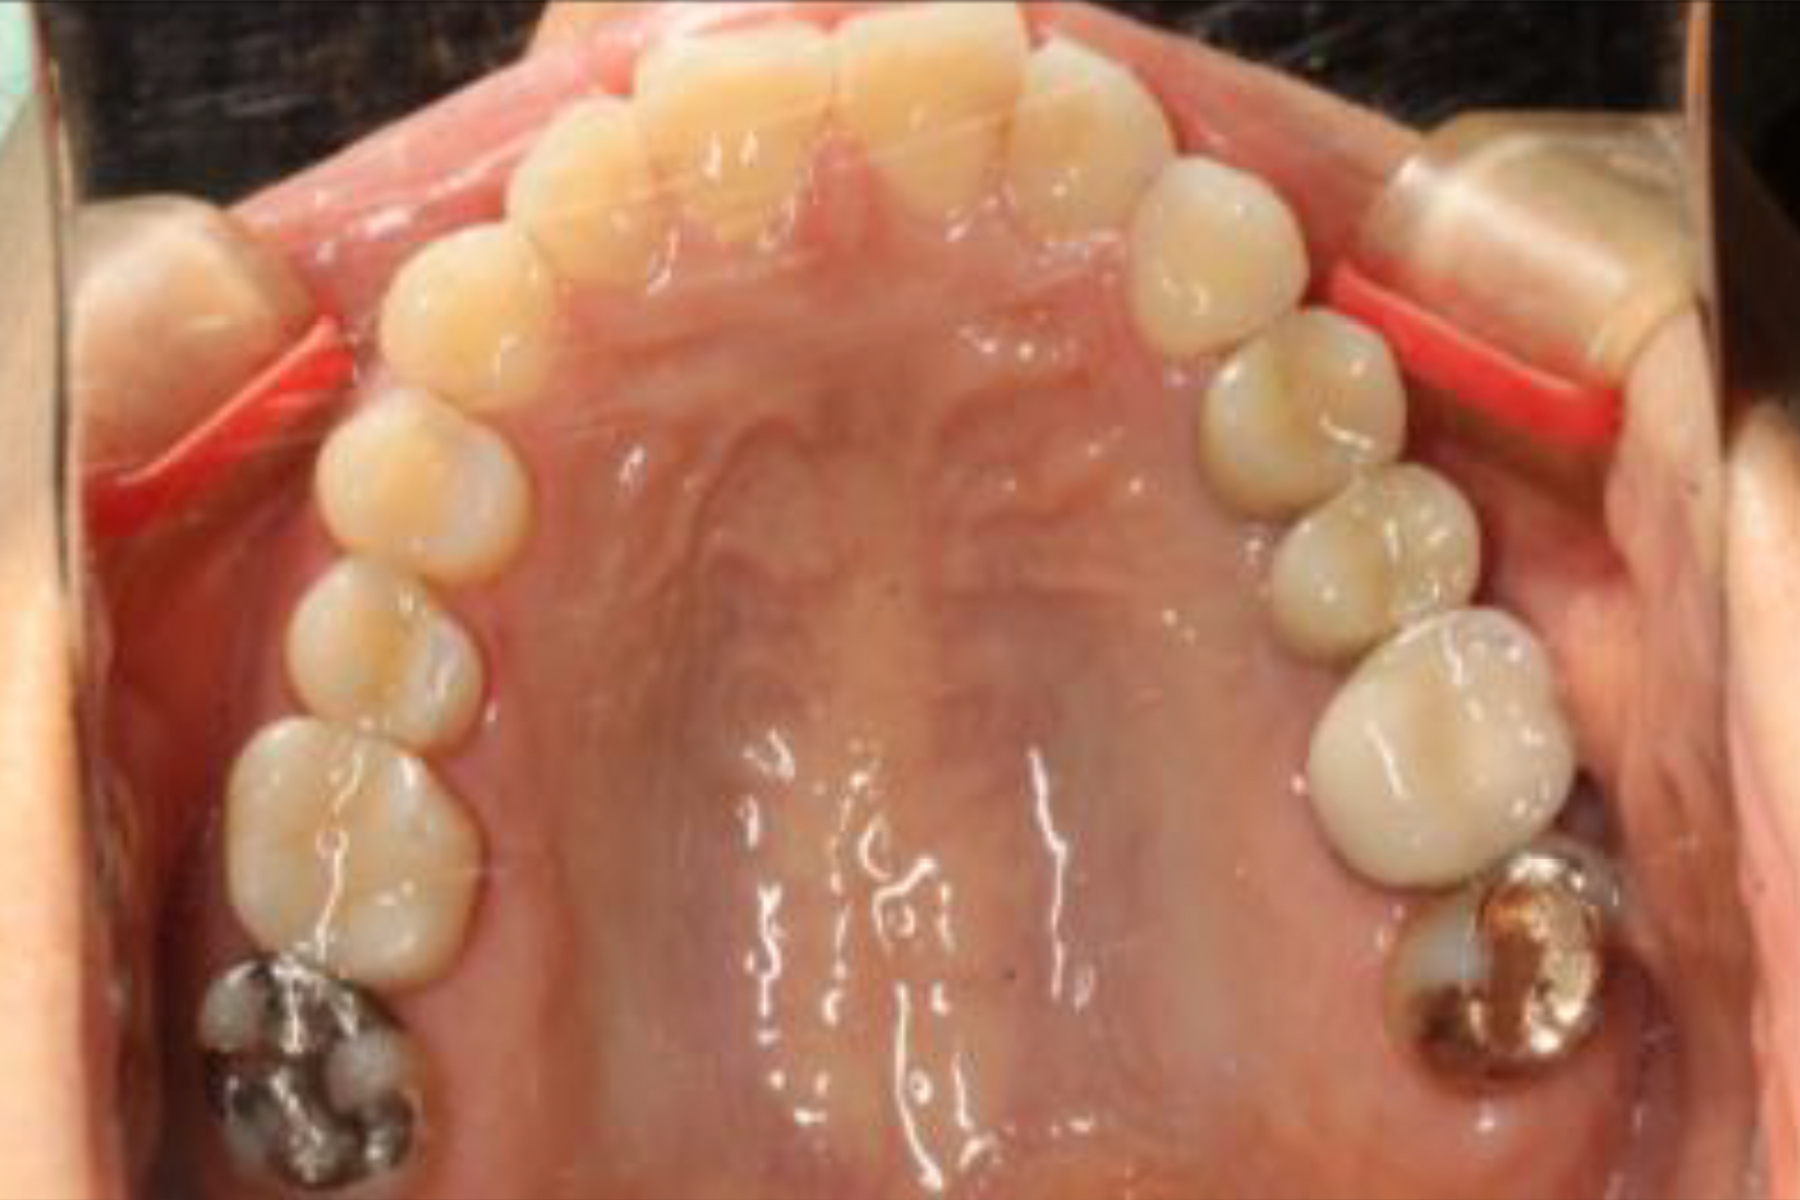

Case.1

BEFORE

AFTER

| 担当医 | 林 大貴 |

|---|---|

| 主訴 | 左上の歯が噛むと痛い |

| 期間 | 約9ヶ月 |

| 治療内容 | 左上4、5番の欠損部位に対して、人工歯根を埋入し上部構造として補綴物をかぶせた。左上4番についてはインプラント埋入の際にソケットリフトを行った。 |

| 治療に伴うリスク | インプラントは、過剰な咬合力がかかった場合、インプラント周囲炎により骨の吸収を認めることがある。 インプラント周囲炎の可能性があるためメンテナンスが必要。 |